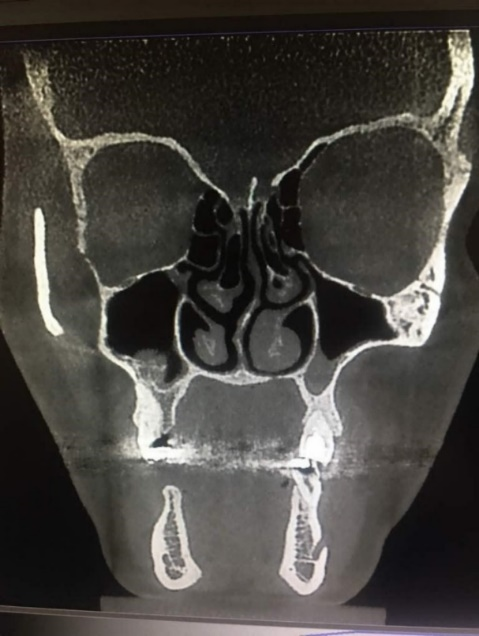

Table 4 shows that in septum types I, VI, II and VII, mucositis was the most common finding. In septum type III, there was one case of normal mucosa. Furthermore, in septum type IV, normal mucosa and sinusitis were more common. In septum type V, sinusitis was the most frequent finding (Figure 3). Chi-squared test did not show any significant difference in the frequency of nasal septum deviation type based on the type of mucosal thickness increase.

Figure 3. S-shaped septal deviation.